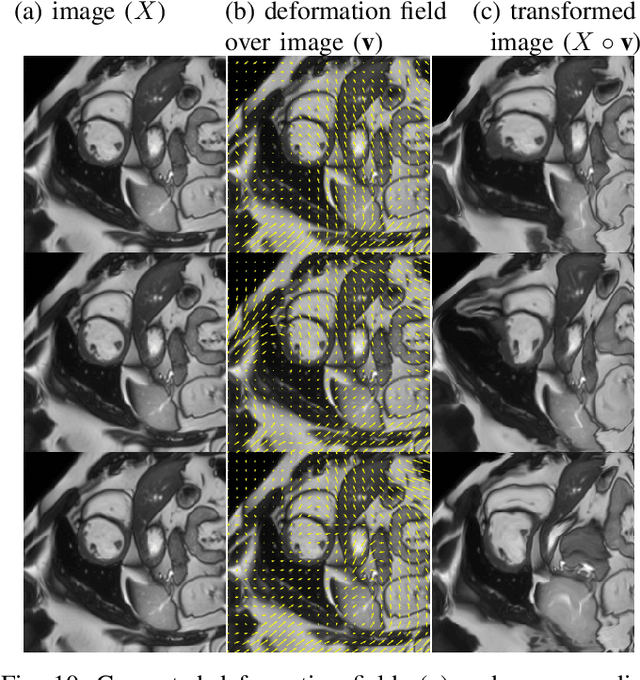

Supervised learning-based segmentation methods typically require a large number of annotated training data to generalize well at test time. In medical applications, curating such datasets is not a favourable option because acquiring a large number of annotated samples from experts is time-consuming and expensive. Consequently, numerous methods have been proposed in the literature for learning with limited annotated examples. Unfortunately, the proposed approaches in the literature have not yet yielded significant gains over random data augmentation for image segmentation, where random augmentations themselves do not yield high accuracy. In this work, we propose a novel task-driven data augmentation method for learning with limited labeled data where the synthetic data generator, is optimized for the segmentation task. The generator of the proposed method models intensity and shape variations using two sets of transformations, as additive intensity transformations and deformation fields. Both transformations are optimized using labeled as well as unlabeled examples in a semi-supervised framework. Our experiments on three medical datasets, namely cardic, prostate and pancreas, show that the proposed approach significantly outperforms standard augmentation and semi-supervised approaches for image segmentation in the limited annotation setting. The code is made publicly available at https://github.com/krishnabits001/task$\_$driven$\_$data$\_$augmentation.